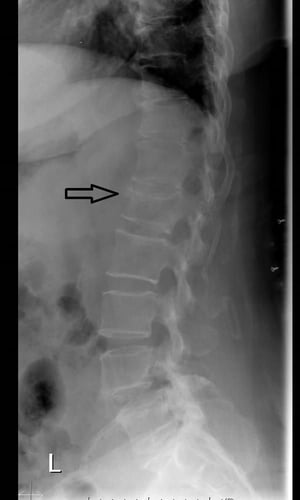

Questa RX laterale della colonna vertebrale mostra perdita di altezza e incuneamento anteriore a causa di una frattura vertebrale da compressione.

Image courtesy of Danielle Campagne, MD.